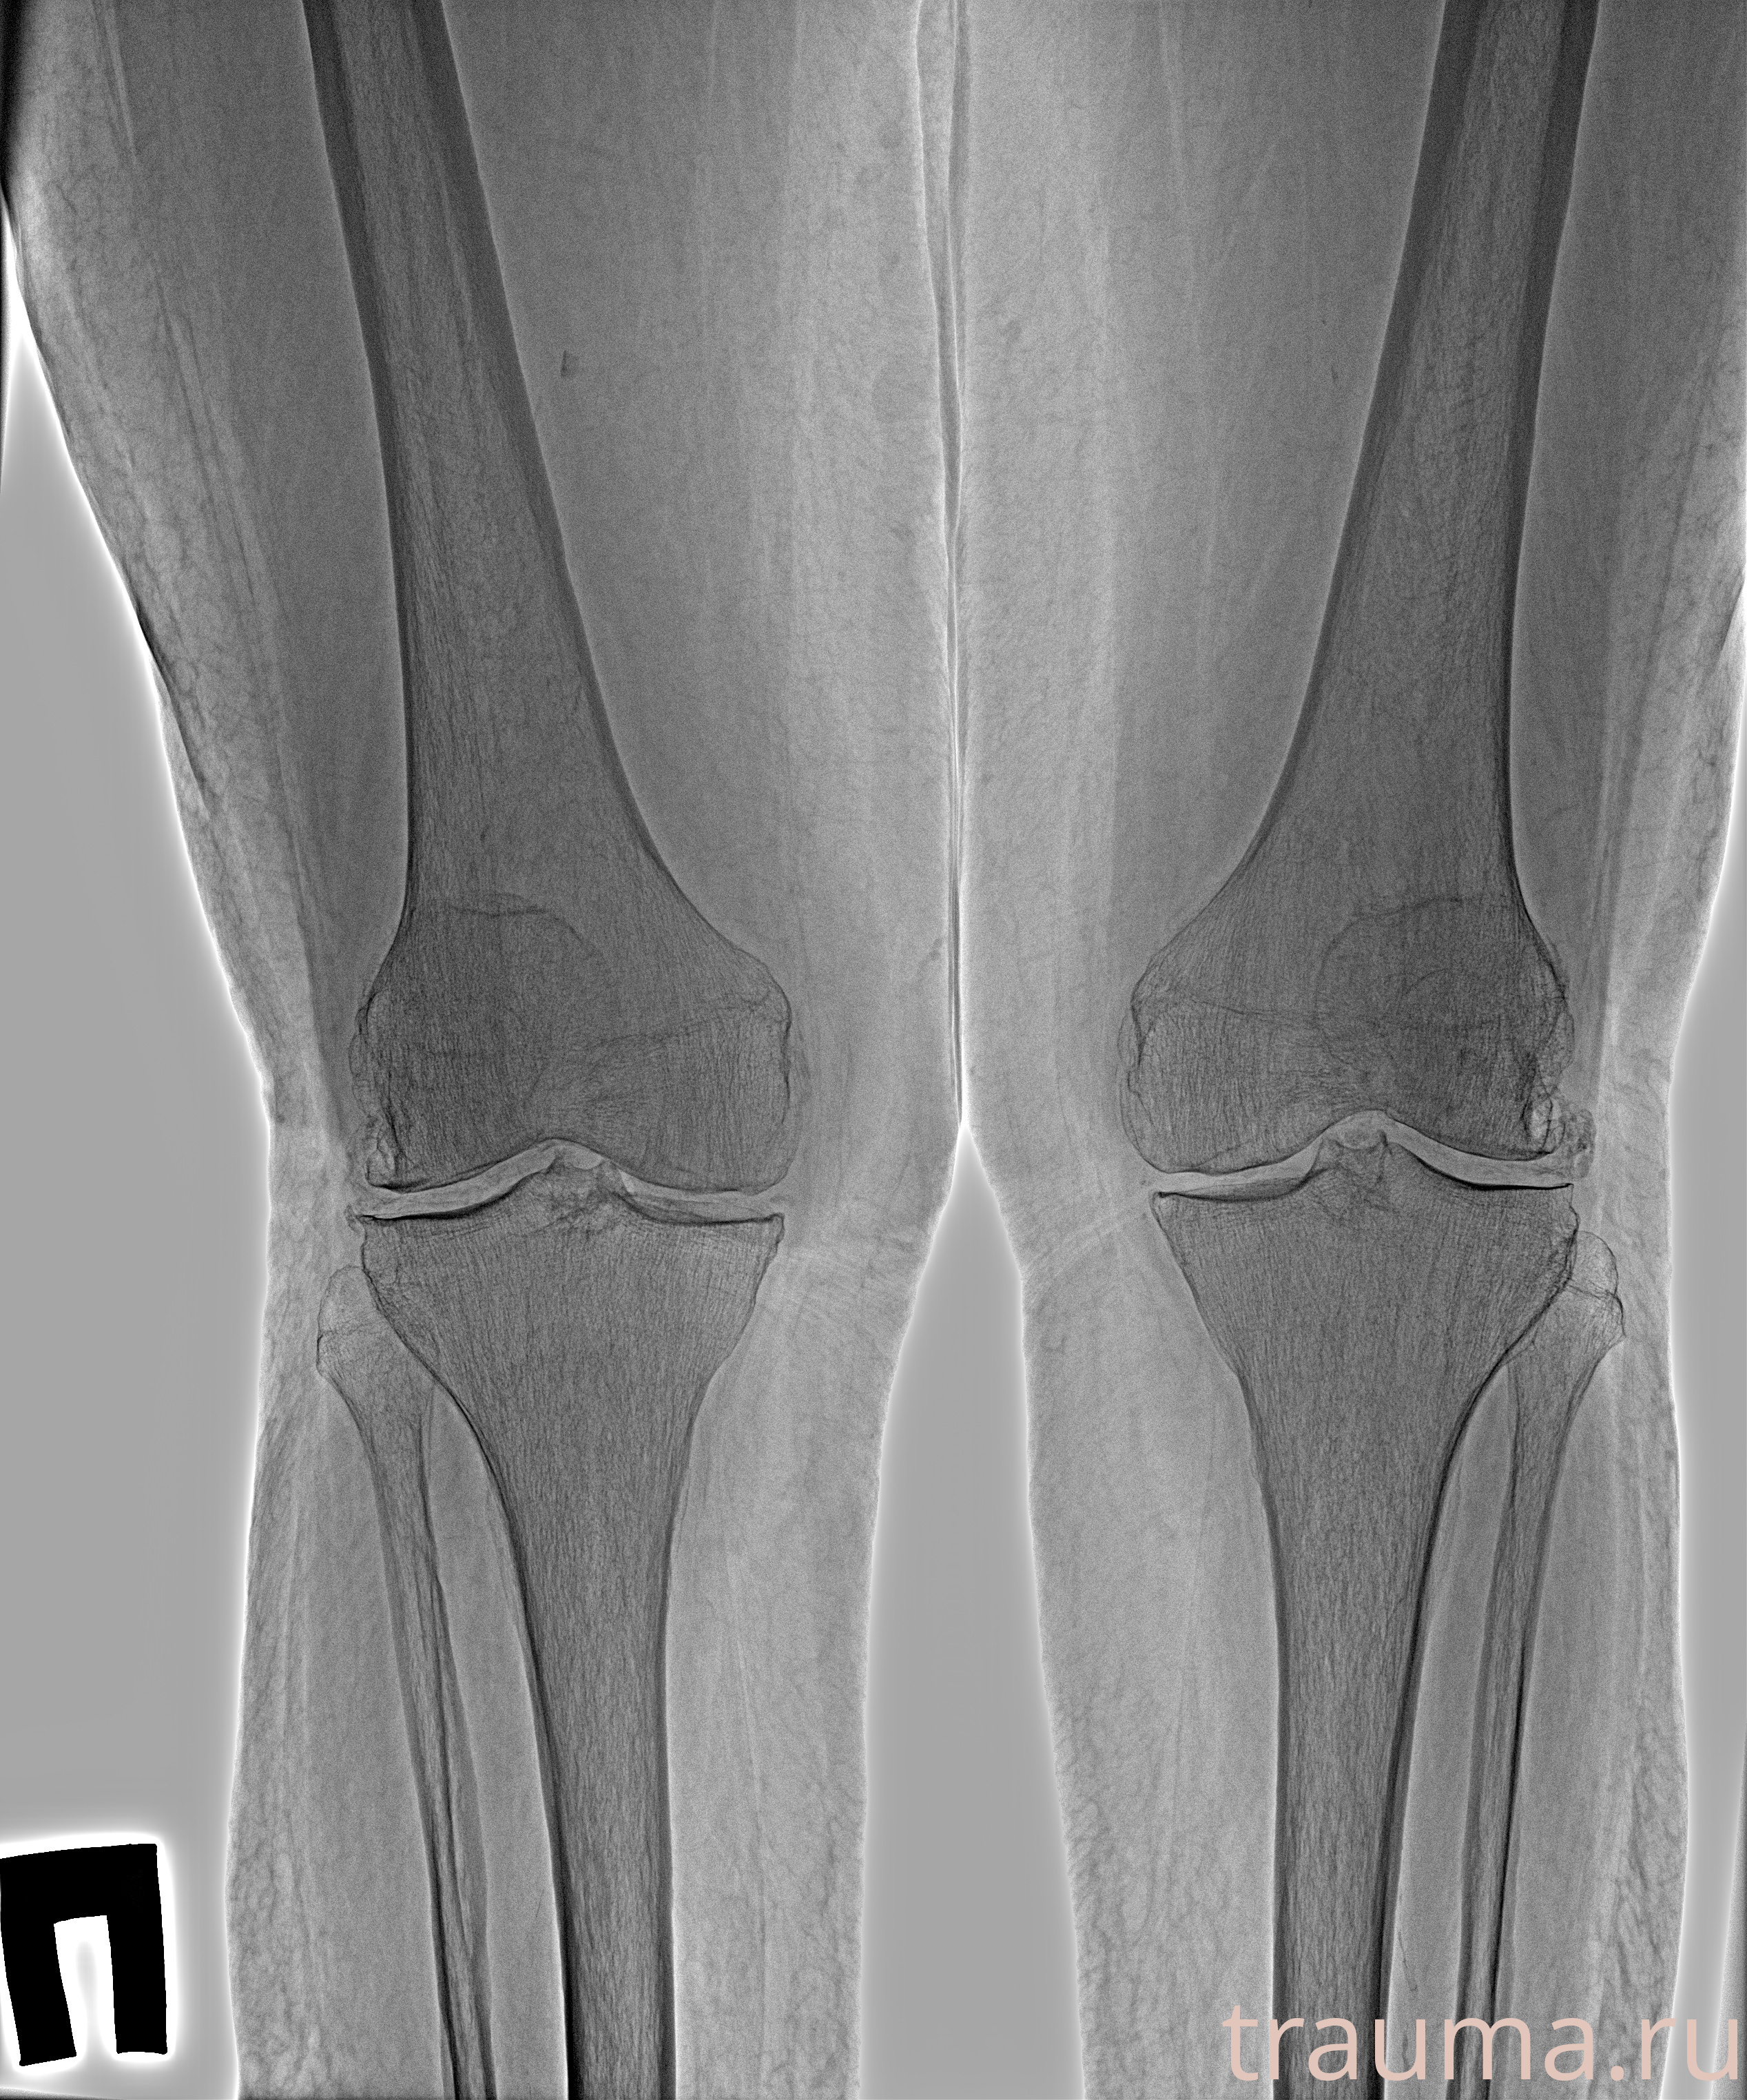

Рентгенограммы